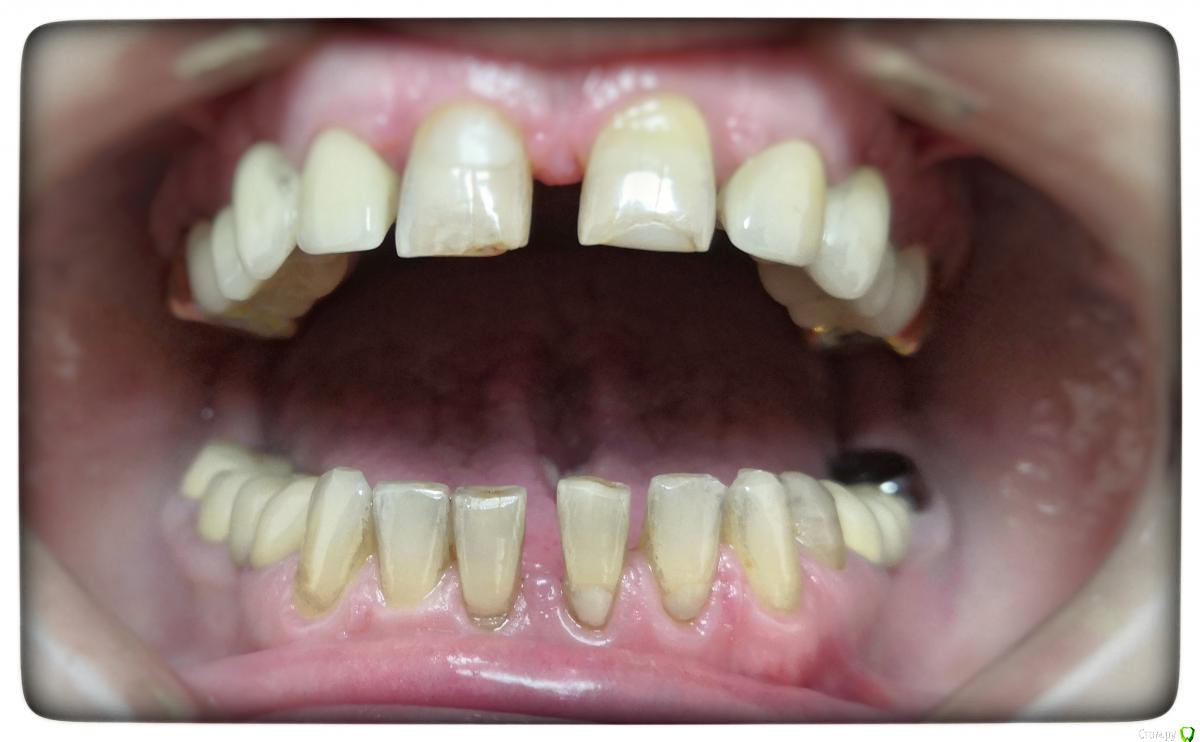

Sagaydak Aleksandr Опубликовано 27 марта, 2019 Поделиться Опубликовано 27 марта, 2019 Здравствуйте. Нужен совет более опытных коллег. Моя первая работа на e.max. Виниры от 3.3 по 4.3. Слепки не получилось снять в день обработки, повторно прокладывать нити в этот день не стал. Сделал времянки, приклеил точечно на адгезив. Назначил через неделю повторно слепки снимать. На повторном приёме пациент жалуется на чувствительность зубов от температурный раздражителей. А теперь вопросы. Должны ли зубы под времянками чувствовать холод и тепло? Будут ли они под постоянными конструкция и чувствовительны? Если будут, то что делать? Как облегчить процесс демонтажа времянок? На повторном приёме потратил на это почти час. Спасибо за внимание. Ссылка на комментарий

Sagaydak Aleksandr Опубликовано 27 марта, 2019 Автор Поделиться Опубликовано 27 марта, 2019 Фото Ссылка на комментарий

Sagaydak Aleksandr Опубликовано 27 марта, 2019 Автор Поделиться Опубликовано 27 марта, 2019 Препарировал через мокап. Ссылка на комментарий